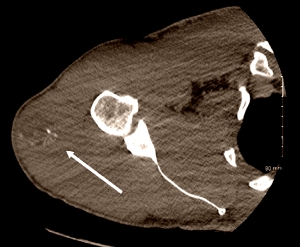

You can see the swelling in the scan below. Myositis ossificans was the diagnosis. The arrow points to an area of calcification.

Myositis ossificans found in steroids user's delts